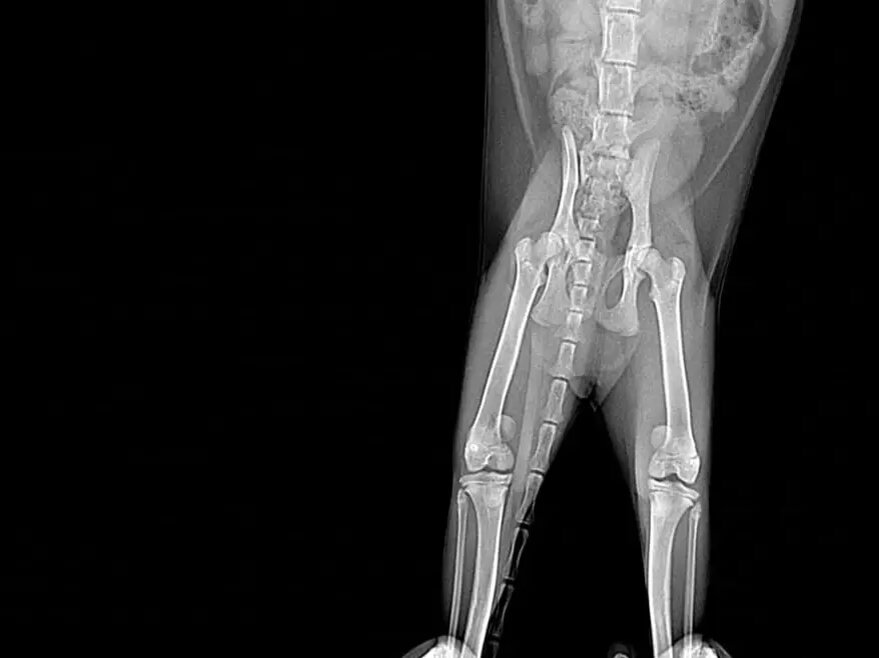

По-началу с котенком все было хорошо — малыш рос и играл, как обычный котенок своего возраста. В какой-то момент питомец стал хромать, а потом и вовсе с трудом ходить. По словам сотрудников приюта, задние лапки у Элоди (так назвали питомца) были в странном положении, и попросту не сгибались.

В ветклинике сообщили шокирующую новость — у малышки врожденный вывих коленных суставов. Если его вовремя не лечить, лапка может неправильно работать, болеть, разрушиться и котенок будет плохо себя чувствовать.

-Ни приют, ни две ветклиники, в которых занимались малышкой, пока не сталкивались с подобными случаями у таких маленьких котят, - подчеркнули волонтеры.

На днях малышу провели первая операция, начали с лапы посложнее. Операция прошла штатно, После Нового года котенку проведут еще одну дорогостоящую операцию.